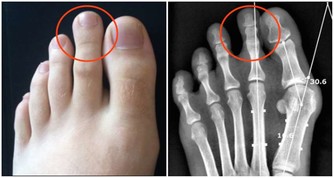

近十幾年來,生薑在紓緩疼痛、輔助治療關節炎上的效果倍受矚目。

風濕病專家在250名骨關節炎患者中進行過一項實驗:

在6週的療程中,一組患者每天兩次服用含有生薑成分的藥物255毫克,另一組患者則服用不含生薑成分的藥物。

2/3服用了含有生薑成分藥物的患者反映,他們感覺病痛減輕,其效果遠遠高於另一組的患者。

貼在疼痛處,可祛風除濕,消腫止痛,輔助治療各種關節炎。

對防治關節炎,寒濕侵襲所致的風濕病、頸椎疼痛等,都有較好治療效果。